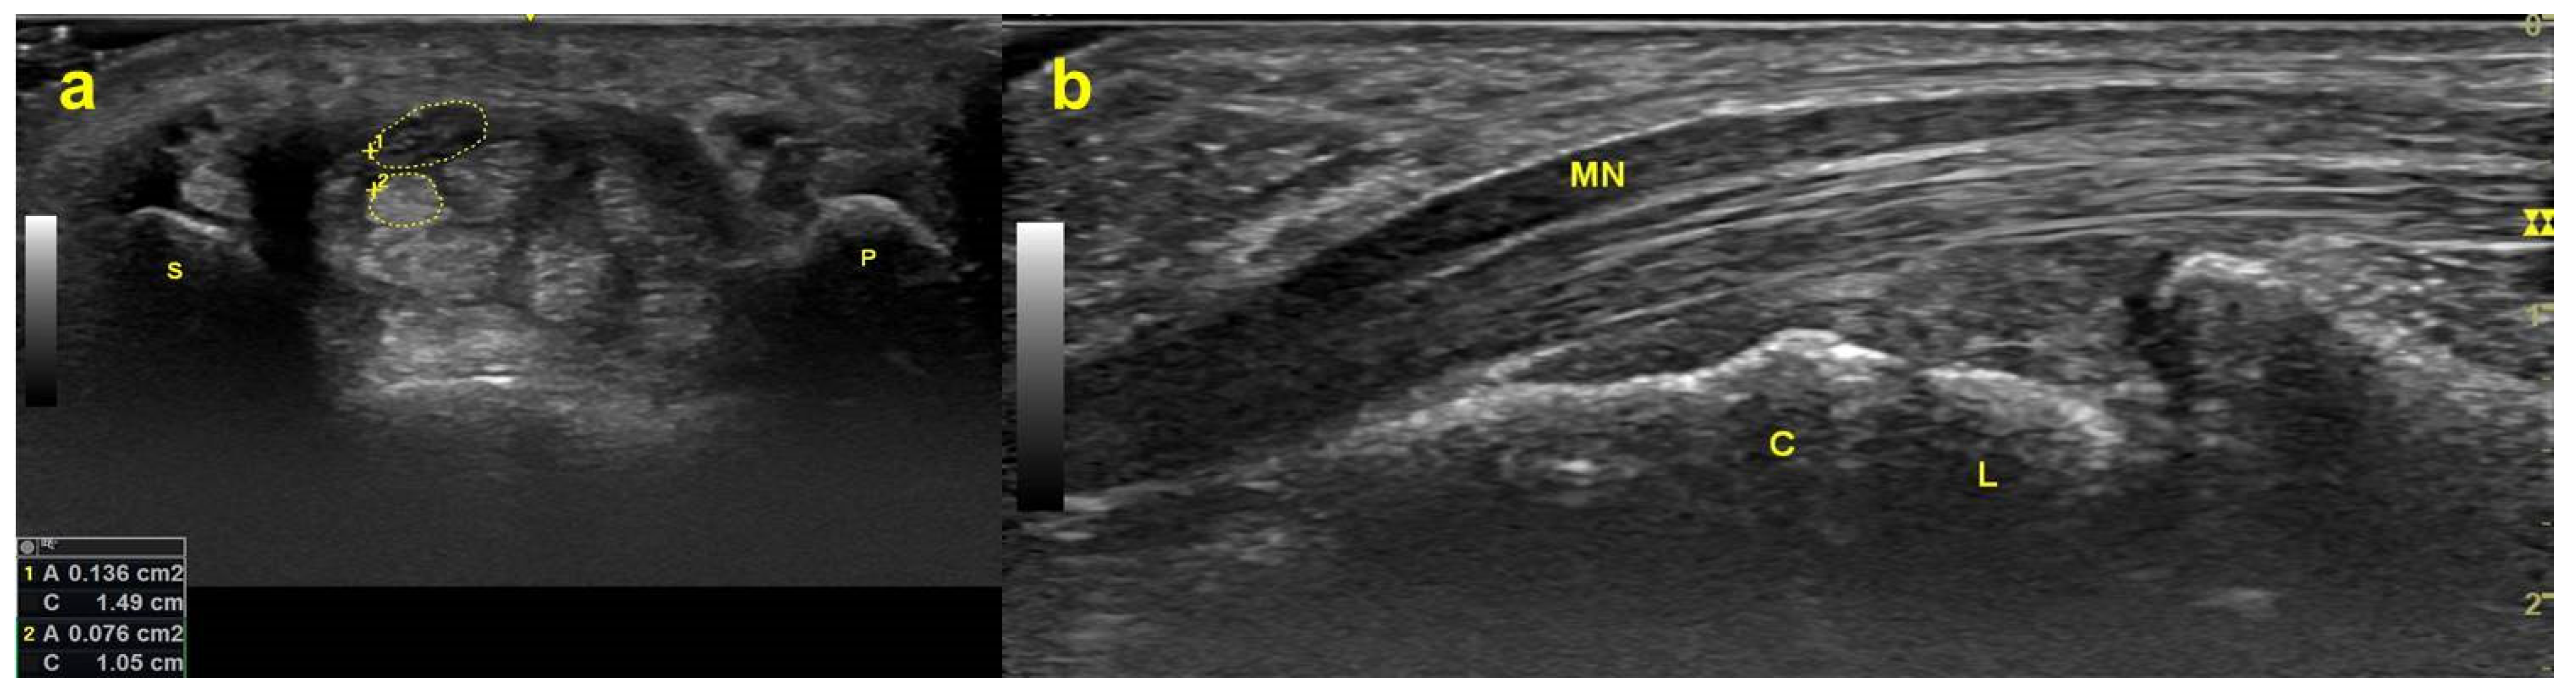

Figure 1. Ultrasonograms captured at the distal wrist crease level. (a) MN (structure enclosed by the upper dotted line) and FDS tendon (structure enclosed by the lower dotted line) in the carpal tunnel on the transverse plane. (b) MN and FDS tendon on the longitudinal plane. Abbreviations: P = pisiform bone; S = scaphoid bone; MN = median nerve; FDS = flexor digitorum superficialis; L = lunate bone; C = capitate bone.

Carpal tunnel syndrome (CTS) is an entrapment neuropathy of the median nerve (MN) inside the carpal tunnel, which is an osteofibrous canal framed by the transcarpal ligament as the roof and the carpal bones as the floor (Figure 1). The MN and nine flexor tendons (the flexor pollicis longus (FPL), the four flexor digitorum superficialis (FDS), and the four flexor digitorum profundus (FDP)) are surrounded and closely connected by subsynovial connective tissue (SSCT), and they travel through the carpal canal together [1] forming a gliding unit [2].